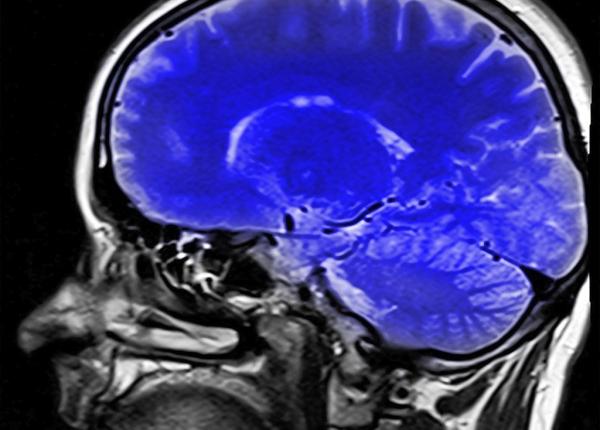

Alzheimer, Parkinson, depresie: depistate prin implant în creier, controlat prin smartphone?

Cercetători au inventat un mic dispozitiv care poate depista boli ale creierului ca Alzheimer, Parkinson. Implantul cerebral este controlat de un smartphone.